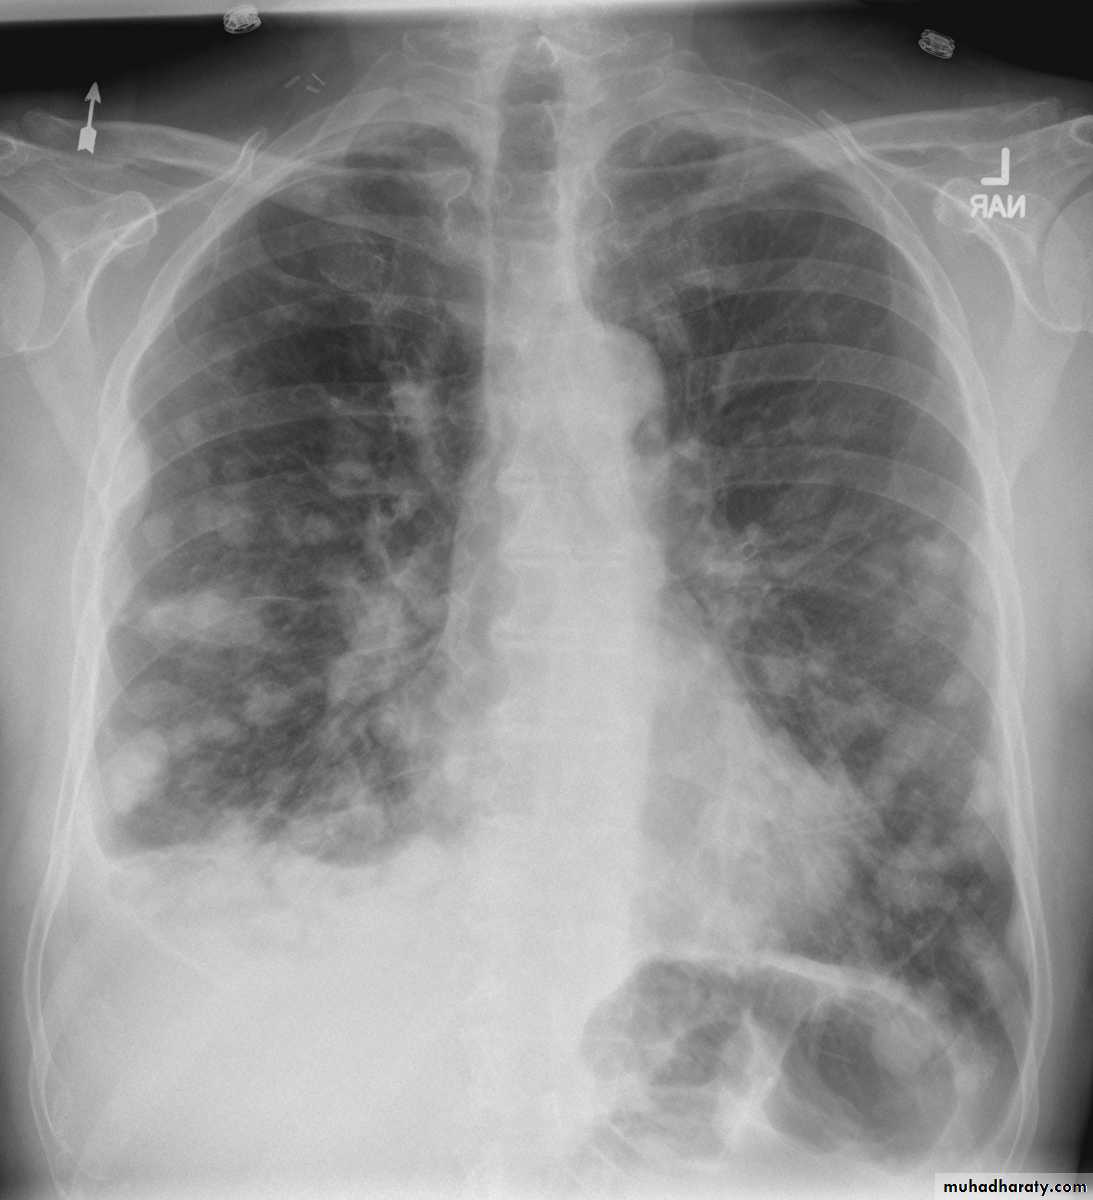

The main aims of investigations are to confirm the diagnosis, establish the histological cell type and define the extent of the disease.1- CXR: common radiological features of lung cancer:

Unilateral hilar enlargement.

Peripheral pulmonary opacity.

Lung, lobe or segmental collapse.

Pleural effusion.

Broadening of mediastinum, enlarged cardiac shadow, elevation of a hemidiaphragm.

Chest radiography shows multiple pulmonary nodules of varying sizes consistent with metastatic cancer.

Multiple and bilateral secondaries